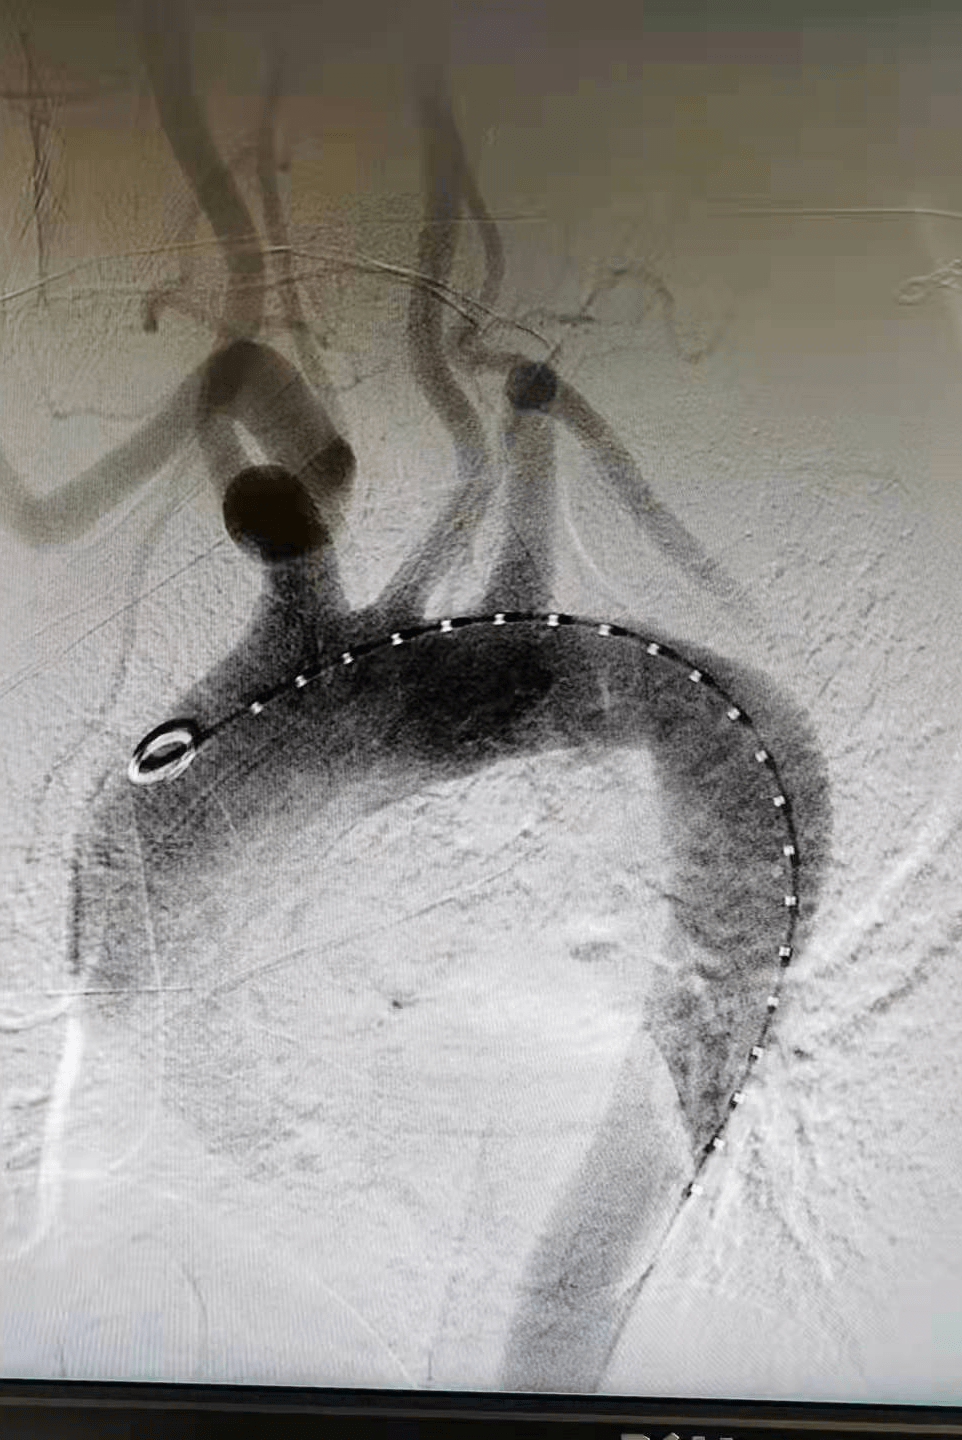

在介入手术室王素娟护士长和付晓慧、陈浩等护士积极配合下 , 刘洪主任带领潘仲杰和郑鹏远两位医生 , 沿患者右侧股总动脉造影(见图二、图三)置入胸主动脉覆膜支架 , 于左颈总动脉的左侧缘 , 先覆盖左侧锁骨下动脉 , 再经左肱动脉进行穿刺 , 用可调弯鞘在左锁骨下动脉开口处体内原位开窗(见图四) , 经球囊扩张窗口(见图五) , 置入球扩覆膜支架(见图六) , 保证了患者主动脉及左锁骨下动脉血流 。

文章图片

(图六)